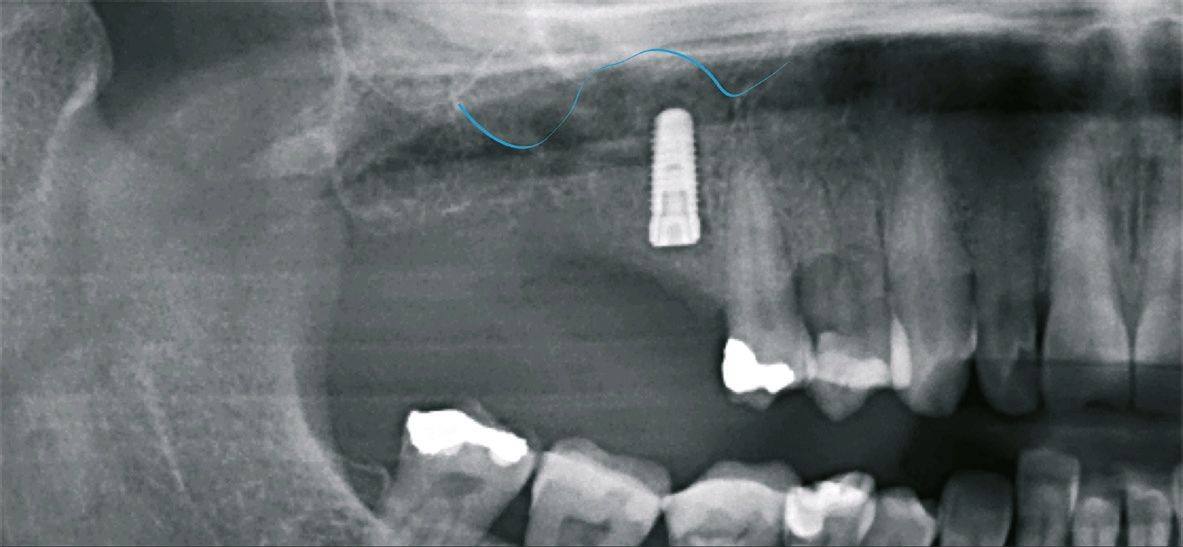

Patient 2: männlich, 71 Jahre alt, Anamnese: koronare Herzkrankheit; Diagnose: zahnloser Kiefer resp. nicht erhaltungswürdiger Zahn 11, insuffizienter Zahnersatz. Knochenersatzmaterial: maxgraft® (botiss) (Abb. 11 und 12).

Dr. van Orten